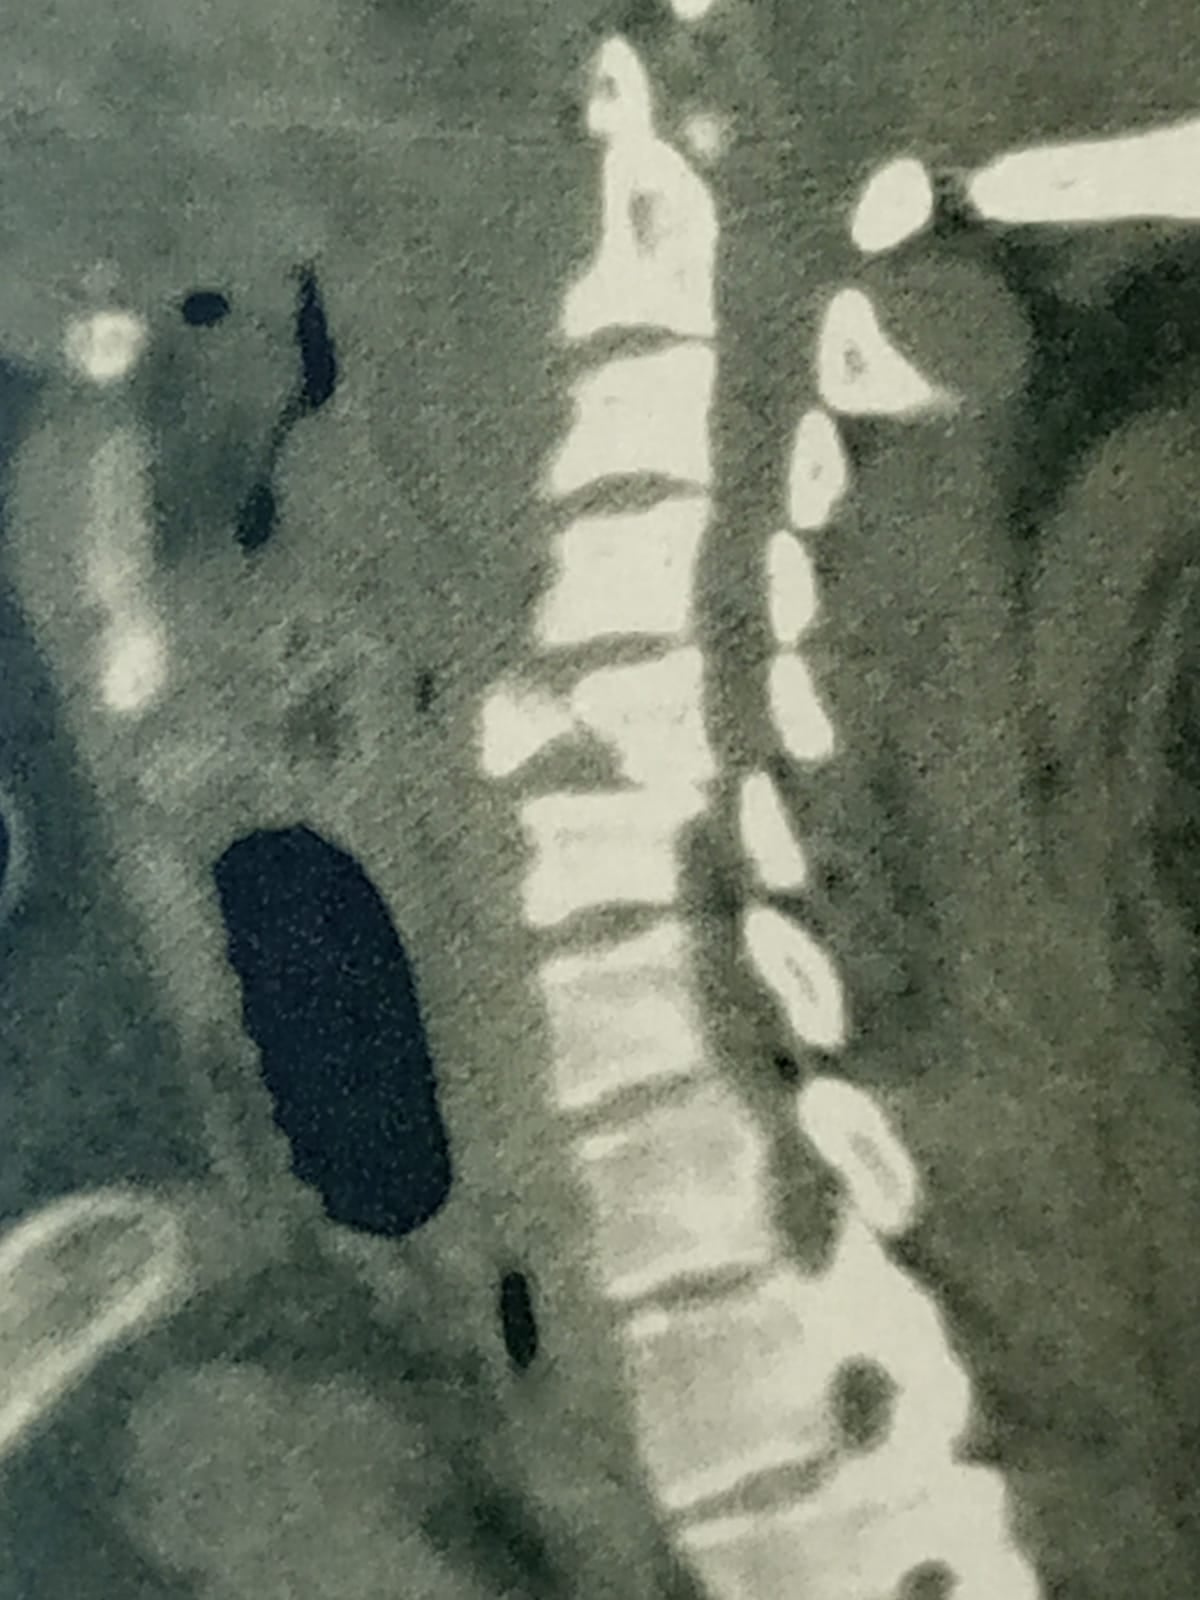

وذكرت مديرية الشؤون الصحية أن مستشفى برج العرب المركزي، الكائنة بغربي الإسكندرية، استقبلت اليوم، مريض، يبلغ من العمر، 40 عامًا، من أحد المستشفيات الخاصة، بتشخيص يشير إلى أن الإصابة عبارة عن كسر متفتت في الفقرة العنقية الخامسة.

وشهدت الجراحة استئصال الفقرة الخامسة «المفتتة» ووضع دعامة عنقية وتثبيتها بواسطة شريحة ومسامير وتوسيع القناة العصبية.